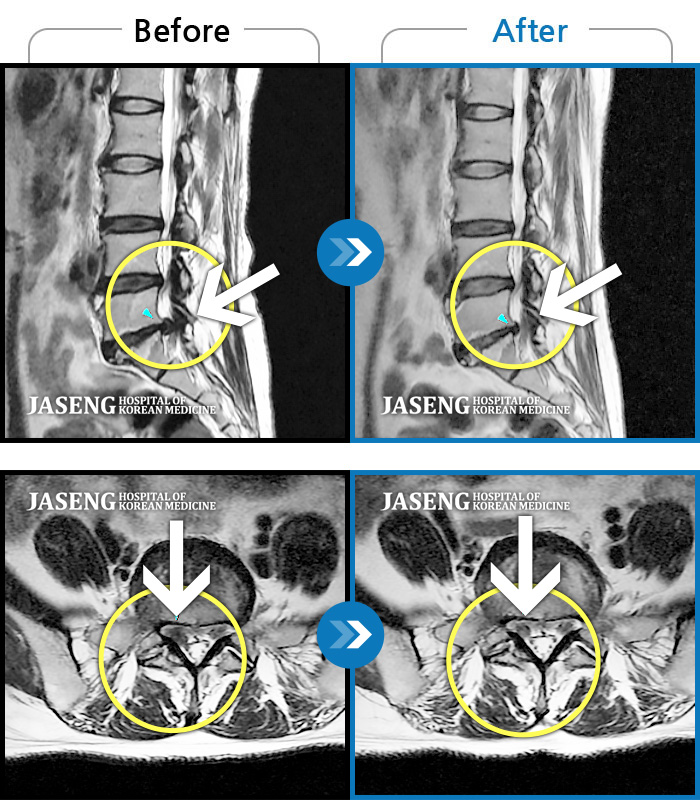

허리디스크

보라매 · 왕오호 원장

허리 통증, 똑바로 서려고 하거나 걸을 때 양쪽 허벅지와 고관절 시큰거림

촬영시기

2017.06.07 ~ 2018.04.17